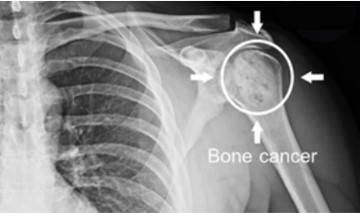

Bone cancer of the shoulder under X-ray.Fig. 1. Bone cancer of the shoulder under X-ray.

Bone cancer is a malignant tumor that occurs in the bone or its adjacent tissues that has a rapid progression and poor prognosis. Bone cancer is mainly classified as primary or secondary which can occur in bone cells, hematopoietic components of bones, cartilage or synovial areas. Primary bone tumors arise from local bone tissue, such as osteosarcoma, chondrosarcoma, and fibrosarcoma. Secondary bone tumors are malignant tumors from other tissues or organs in the body that metastasize to the bone through the blood circulation and lymphatic system. Bone cancer has the highest mortality rate among bone diseases, and is currently a hot research area among cancers.